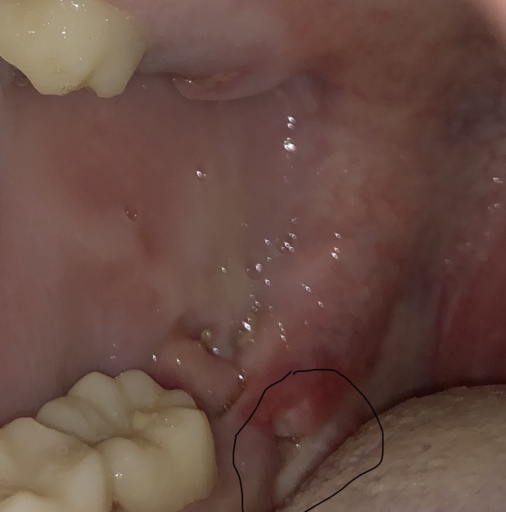

Teeth bent and twisted and a lot of pain given

For a long time I have been expriencing a lot of pain I'm my teeth when I eat drink and not do anything with them, when I eat I go through a lot of pain and feel sick and light headed because of it. My teeth are twisted and bent and one of them which is my adult tooth and another one which is my adult tooth feels like it's going to fall out which gives me more pain as they have been pushed backwards and forwards and I'm looking on some advice to do.